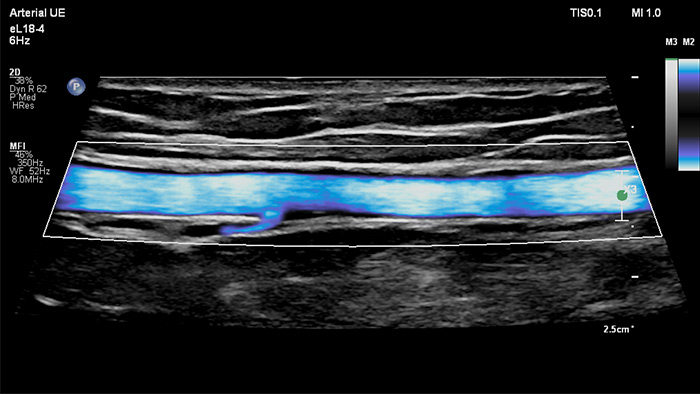

MicroFlow Imagingは、組織内の低流速かつ微細な血流を高感度で検出し、血管検査におけるフロー分解能を強化します。高分解能と最小限のアーチファクトにより、臨床医は狭窄プラーク周辺のわずかな血流障害を描出して特性を評価し、確実な診断を行えます。